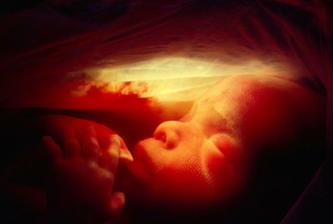

S blížícím se koncem těhotenství se zvyšuje i netrpělivost. Objevuje se obava ze samotného porodu a z faktu příchodu nového člena rodiny.

- III. trimestr = 29. - 40. týden těhotenství